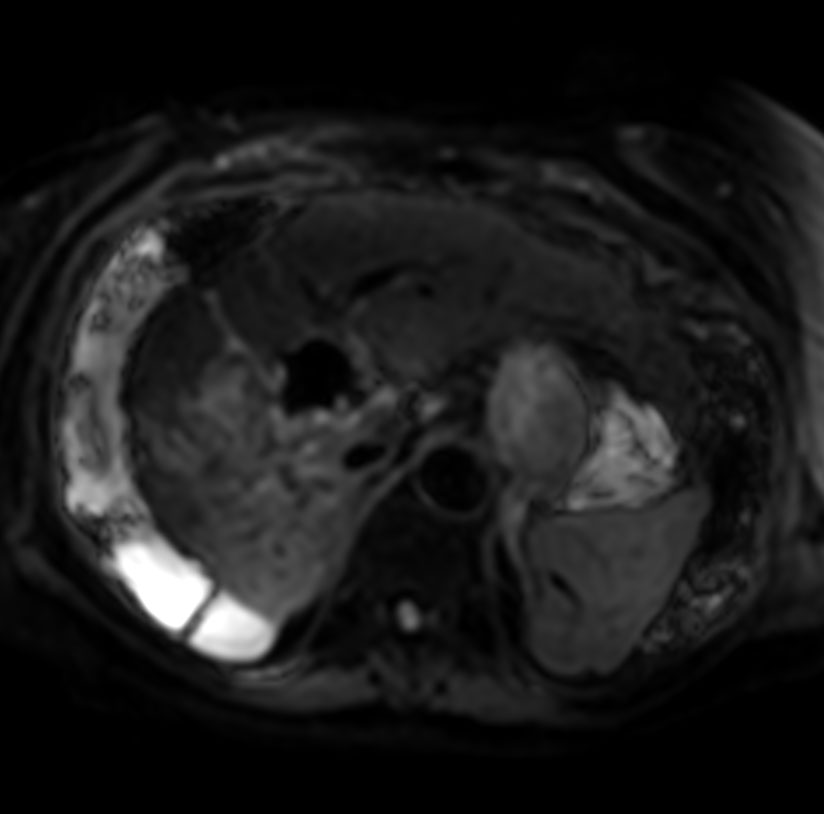

Axial T1w mDIXON XD FFE (1st dynamic)